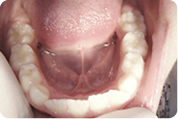

Intraoralna kamera

Prikaz zuba intraoralnom kamerom pod povećanjem i do 60 puta omogućuje nam uvid u stanje svakog pojedinog zuba i precizno planiranje radova. Jednako tako važna je i mogućnost jasnog prikaza zubnih lukova u cjelini i prikaza plana terapije našim pacijentima.